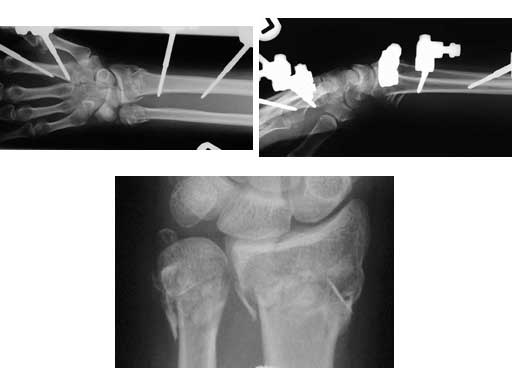

A 48-year-old female had an accident while on vacation. Local temporary treatment was performed with a bridging external fixator and definitive treatment with a plate 2 weeks postinjury.

Fig 1ac Preoperative x-rays (AP, lateral, close-up).